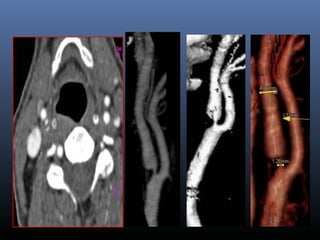

CTA

▪ Fast, thin section,volumetric spiralCT

examination performed with a time-

optimized bolus of contrast material for the

opacification of vessels.

CTA- Source images

▪ Occlusion ,stenosis or

significant calcification

of an Extracranial

internal carotid artery

▪ Detection of hyperacute

infarct

▪ Substraction perfusion

CTA- adv

▪ Volume rendering.

▪ Groups of voxels within defined attenuation

thresholds are selected,and a color as well as

an “opacity” is assigned

MIP

SSD

VRT

Basilar artery

calcifications

CTA- comparison

▪ Degree of stenosis-Axial,VR images

▪ Calcification- axial, MIP

▪ Anatomical, spacial relationship-axial,VRT